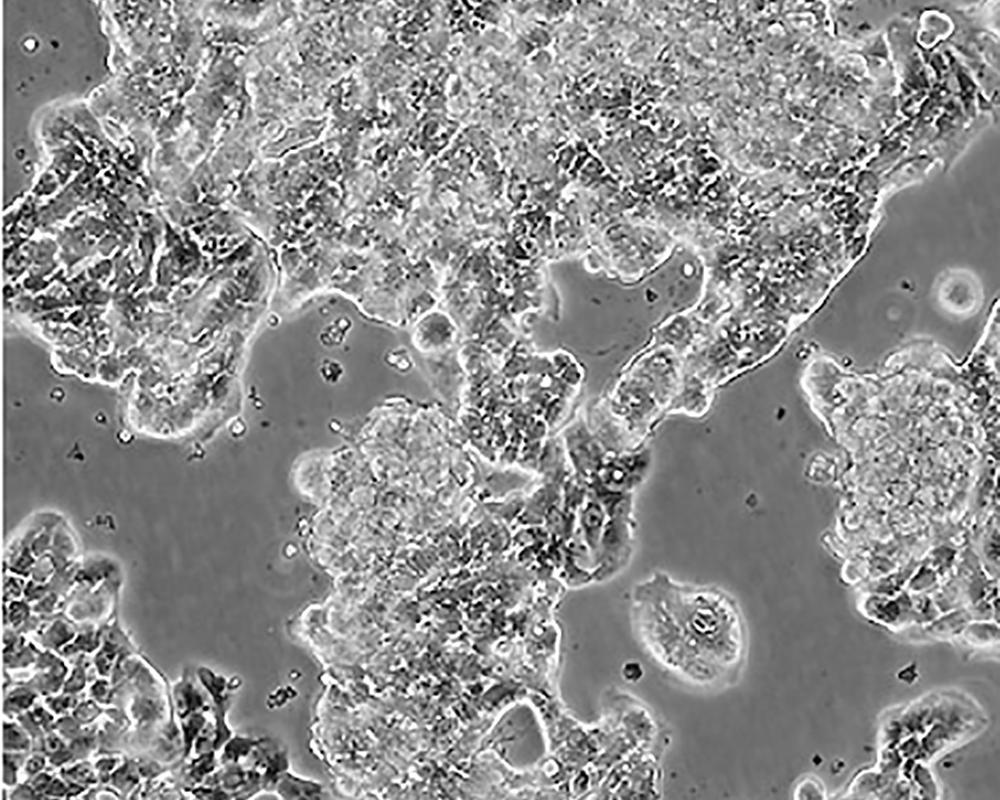

生長特性 adherent

形態特征 epithelial

傳代方法 1:2-1:3

細胞描述 該細胞產生高水平的黏液素MUC-1 mRNA,低水平的MUC-2 mRNA,但不表達MUC-3基因;表達雌激素受體。

細胞傳代步驟 如果細胞密度達80%-90%,即可進行傳代培養。1. 棄去培養上清,用不含鈣、鎂離子的PBS潤洗細胞1-2次。2. 加2ml消化液(0.25%Trypsin-0.53mM EDTA)于培養瓶中,置于37℃培養箱中消化1-2分鐘,然后在顯微鏡下觀察細胞消化情況,若細胞大部分變圓并脫落,迅速拿回操作臺,輕敲幾下培養瓶后加少量培養基終止消化。3. 按6-8ml/瓶補加培養基,輕輕打勻后吸出,在1000RPM條件下離心4分鐘,棄去上清液,補加1-2mL培養液后吹勻。4. 將細胞懸液按1:2到1:5的比例分到新的含8ml培養基的新皿中或者瓶中